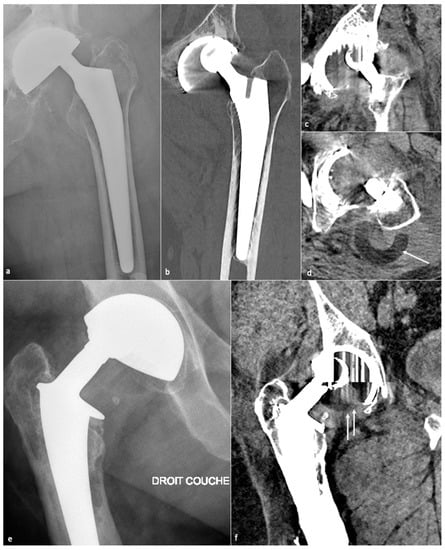

- Metallosis results from the shedding of metallic debris (secondary to a MoM prosthesis with corrosion, a conflict between a metallic acetabular cup and the prosthetic neck, or a contact between a metallic head and an acetabular metal back in case of PE wear or dislocation) that induces synovitis and an indolent pattern of osteolysis, potentially leading to loosening (i.e., potentially looking similar to osteolysis and PE wear). Synovitis may contain low-signal intensity or metallic density debris, causing MRI artifacts and bone erosion, best depicted on CT-MAR (Figure 20). Such debris might also be located in periprosthetic soft tissue and lymph nodes [54,57]. Metallic debris presence might also accentuate PE wear (i.e., third fragment wear) [54]. Of note, high serum metal-ion levels can be found in symptomatic and asymptomatic patients and would be associated with pseudo-tumors, so that such a biological finding should lead to the prescription of an MRI to rule out a pseudo-tumor even in asymptomatic patients [6,103].

- Additionally, referred to as trunnionosis, trunnion corrosion corresponds to a soft-tissue reaction to metal debris released from micromotion and mechanical wear at the head–neck or neck–stem junction of modular MoP HA. On MRI, it manifests as an adverse local reaction associated with medial calcar resorption [11,104].